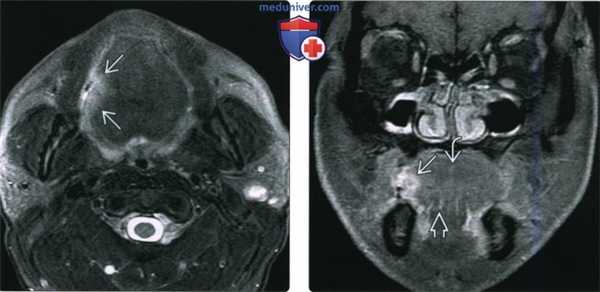

(Слева) При МРТ Т1ВИ С + FS в аксиальной проекции у этого же пациента не четко визуализируется объемное образование передних отделов дна полости рта, прорастающее в правую подъязычную железу. Обратите внимание на отсутствие кортикальной пластинки с гипоинтенсивным сигналом в прилежащих отделах нижней челюсти, что подтверждается и при КТ в костном окне. Патологически измененные лимфоузлы не определяются.

(Справа) На фото этого же пациента, полученном при клиническом обследовании, также видна опухоль в передних отделах дна полости рта. Фото позволяет оценить локализацию опухоли и подъязычных желез. На операции была подтверждена опухоль T4aN0 с инвазией нижней челюсти.

(Слева) При MPT Т2ВИ FS в аксиальной проекции визуализируется небольшая опухоль в боковых отделах языка справа, выглядящая как двояковыпуклый участок с сигналом повышенной интенсивности и с типичными нечеткими краями, недостигающий средней линии.

(Справа) Корональная томограмма (Т1ВИ С+ FS) этого же пациента, язва в боковых отделах языка накапливает контраст. Опухоль не распространяется книзу в подбородочно-язычную мышцу или в другие наружные мышцы языка, и не достигает срединно расположенной язычной перегородки. Была выполнена гемиглоссэктомия и селективная шейная лимфодиссекция, подтвердился ПКР (Т1 N0, первая стадия).